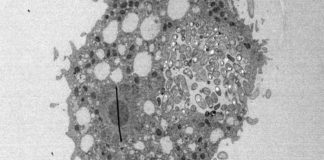

La yersinia pestis es una bacteria que tiene el dudoso honor de ser la segunda más causante de muertes humanas a lo largo de la historia, tan sólo después de los parásitos del género Plasmodium, causantes de la malaria. Durante el Imperio bizantino, en época de Justiniano I (siglos V y VI), se produjo el primer brote de peste bubónica conocido, que acabó con la vida, se cree, de más de 50 millones de personas en Europa. Sin embargo, el brote más conocido y terrorífico de peste se dio en Europa en el siglo XIV, durante el cual se estima que falleció un tercio de la población humana del planeta (aunque afectó solamente a Europa y parte de Asia). El tercer brote tuvo lugar en el siglo XIX en Asia Oriental, matando a más de 12 millones de personas en la India durante 1986.

El estudio se centra en la región de Samara, en Rusia, donde las tumbas han arrojado material humano que, tras ser analizado genéticamente, muestra signos de persistencia de la bacteria yarsinia pestis ya desde una era temprana y con extrema virulencia, lo que sugiere que ya en la Edad del Bronce existió una primera plaga de peste que asoló la región mucho antes de que llegase desde el Imperio bizantino.

La peste bubónica se transmite por las pulgas y para convertirse en plaga necesita unas características concretas, que sí han sido encontradas en la variedad de yersinia pestis aparecida en Samara. Según la doctora Maria Spyrou, autora del estudio, las bacterias encontradas en Samara tienen una persistencia temporal hasta nuestros días.